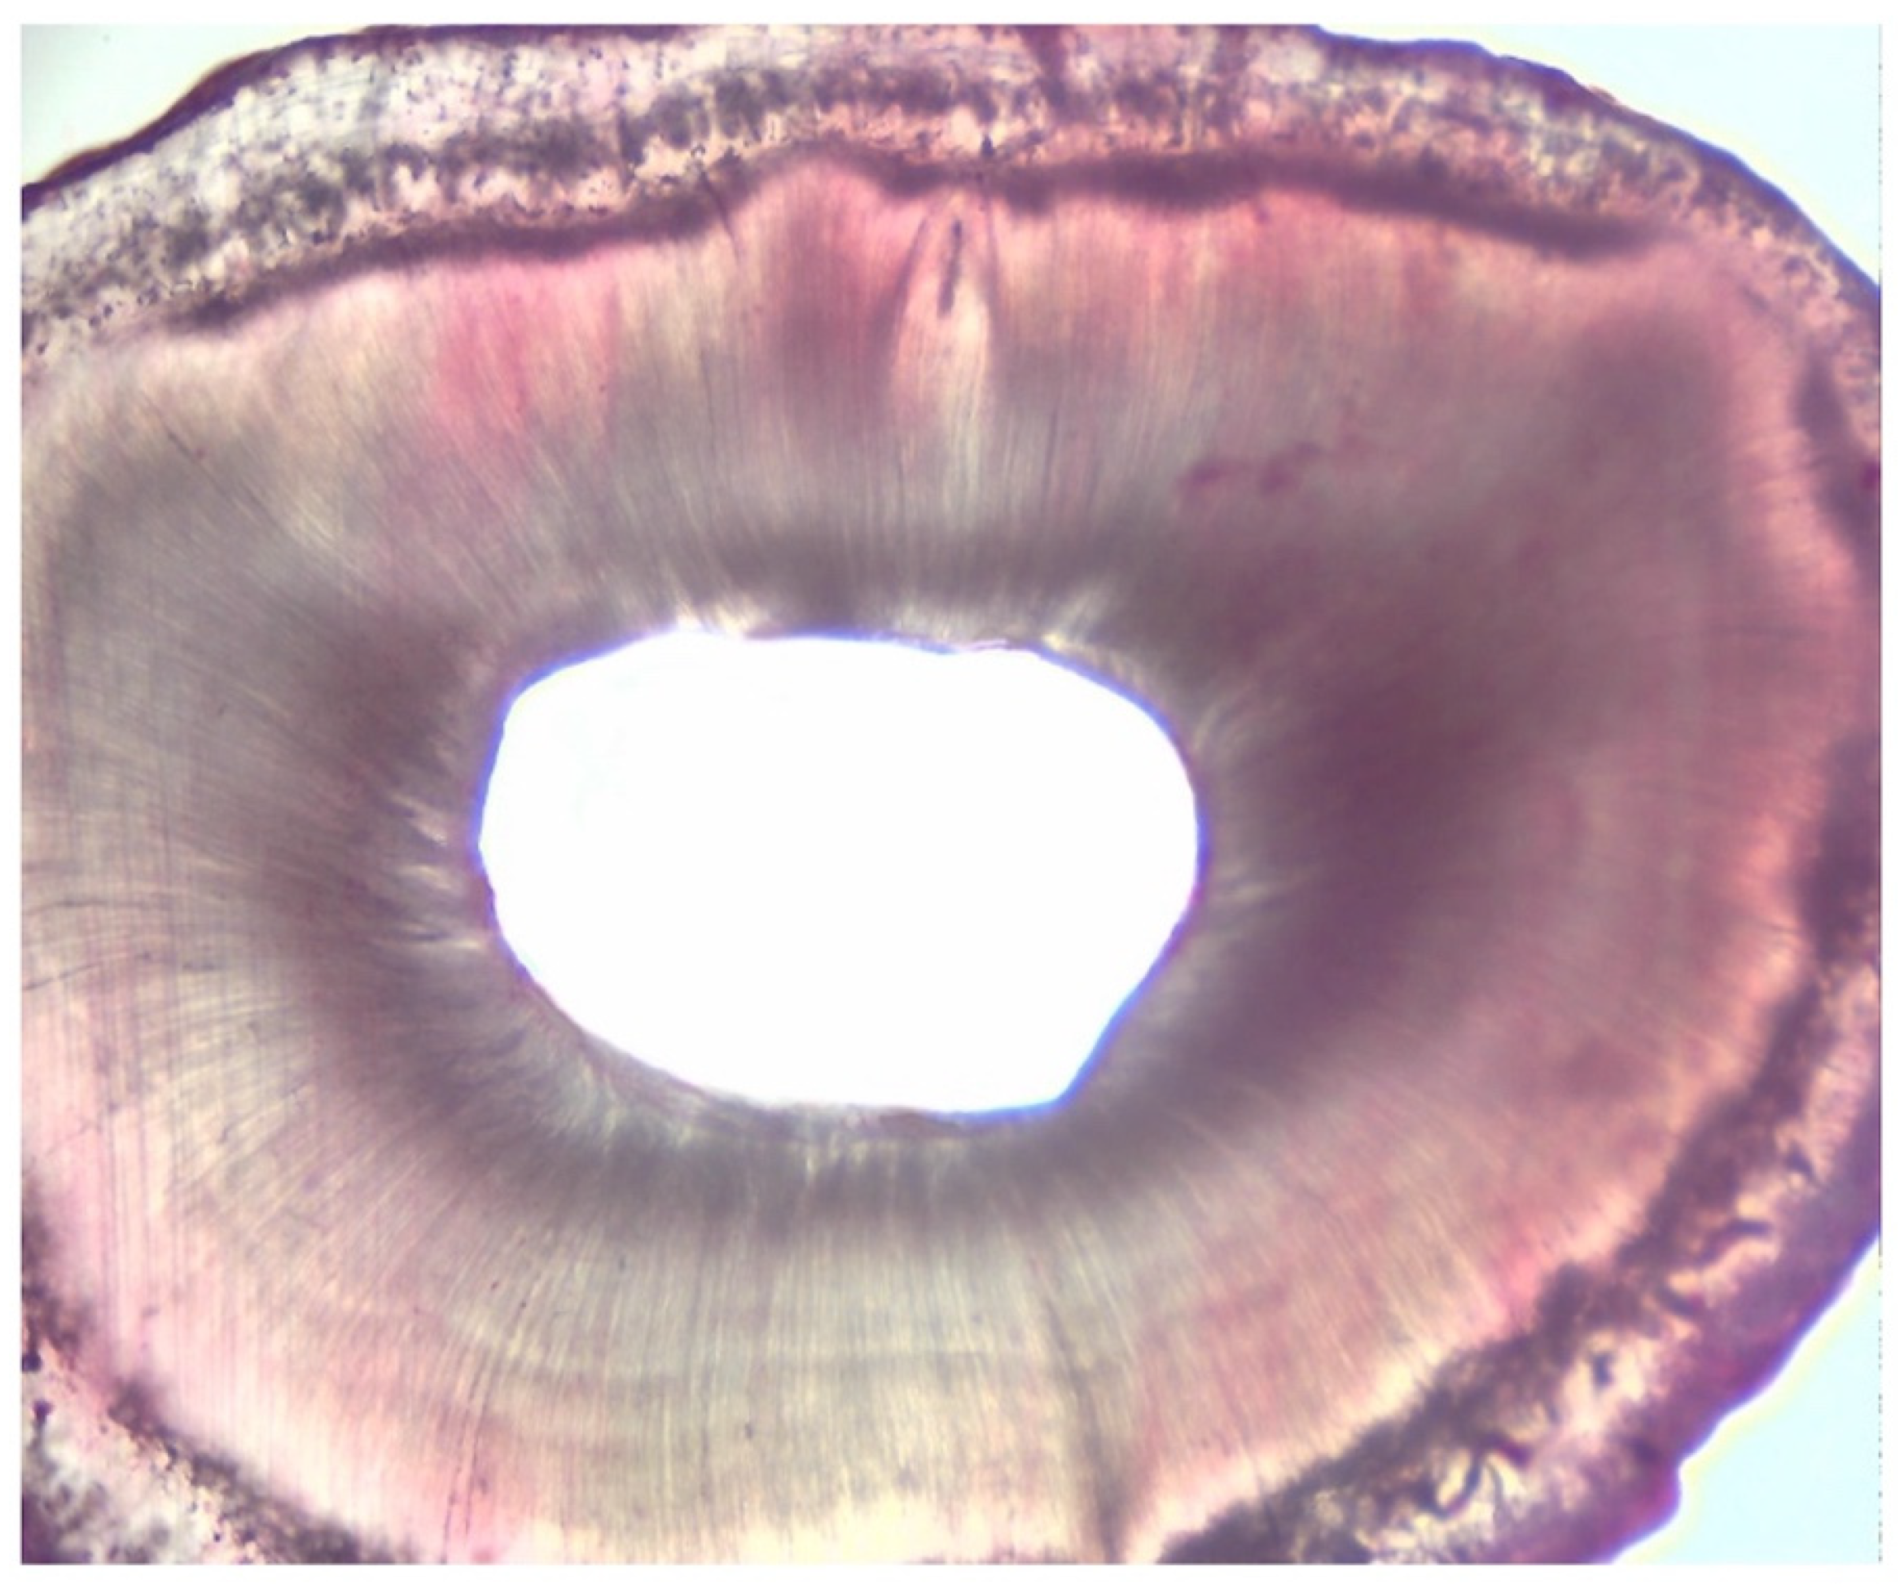

2.3. Assessment of Root Canal Cleanliness

| Grading | |

|---|---|

| I | presence of debris within the area |

| II | presence of debris in more than 50% of the entire area |

| III | presence of debris in more than 25% of the entire area |

| IV | absence of debris or presence of debris in less than 25% of the entire area |

| Score | III | IV | IV | III | IV | III | III | IV | III | IV | IV | III | IV | IV | III | III | IV | IV | IV | IV |